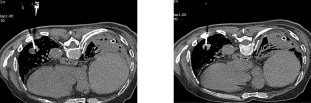

术中射频消融通路(一) (二)